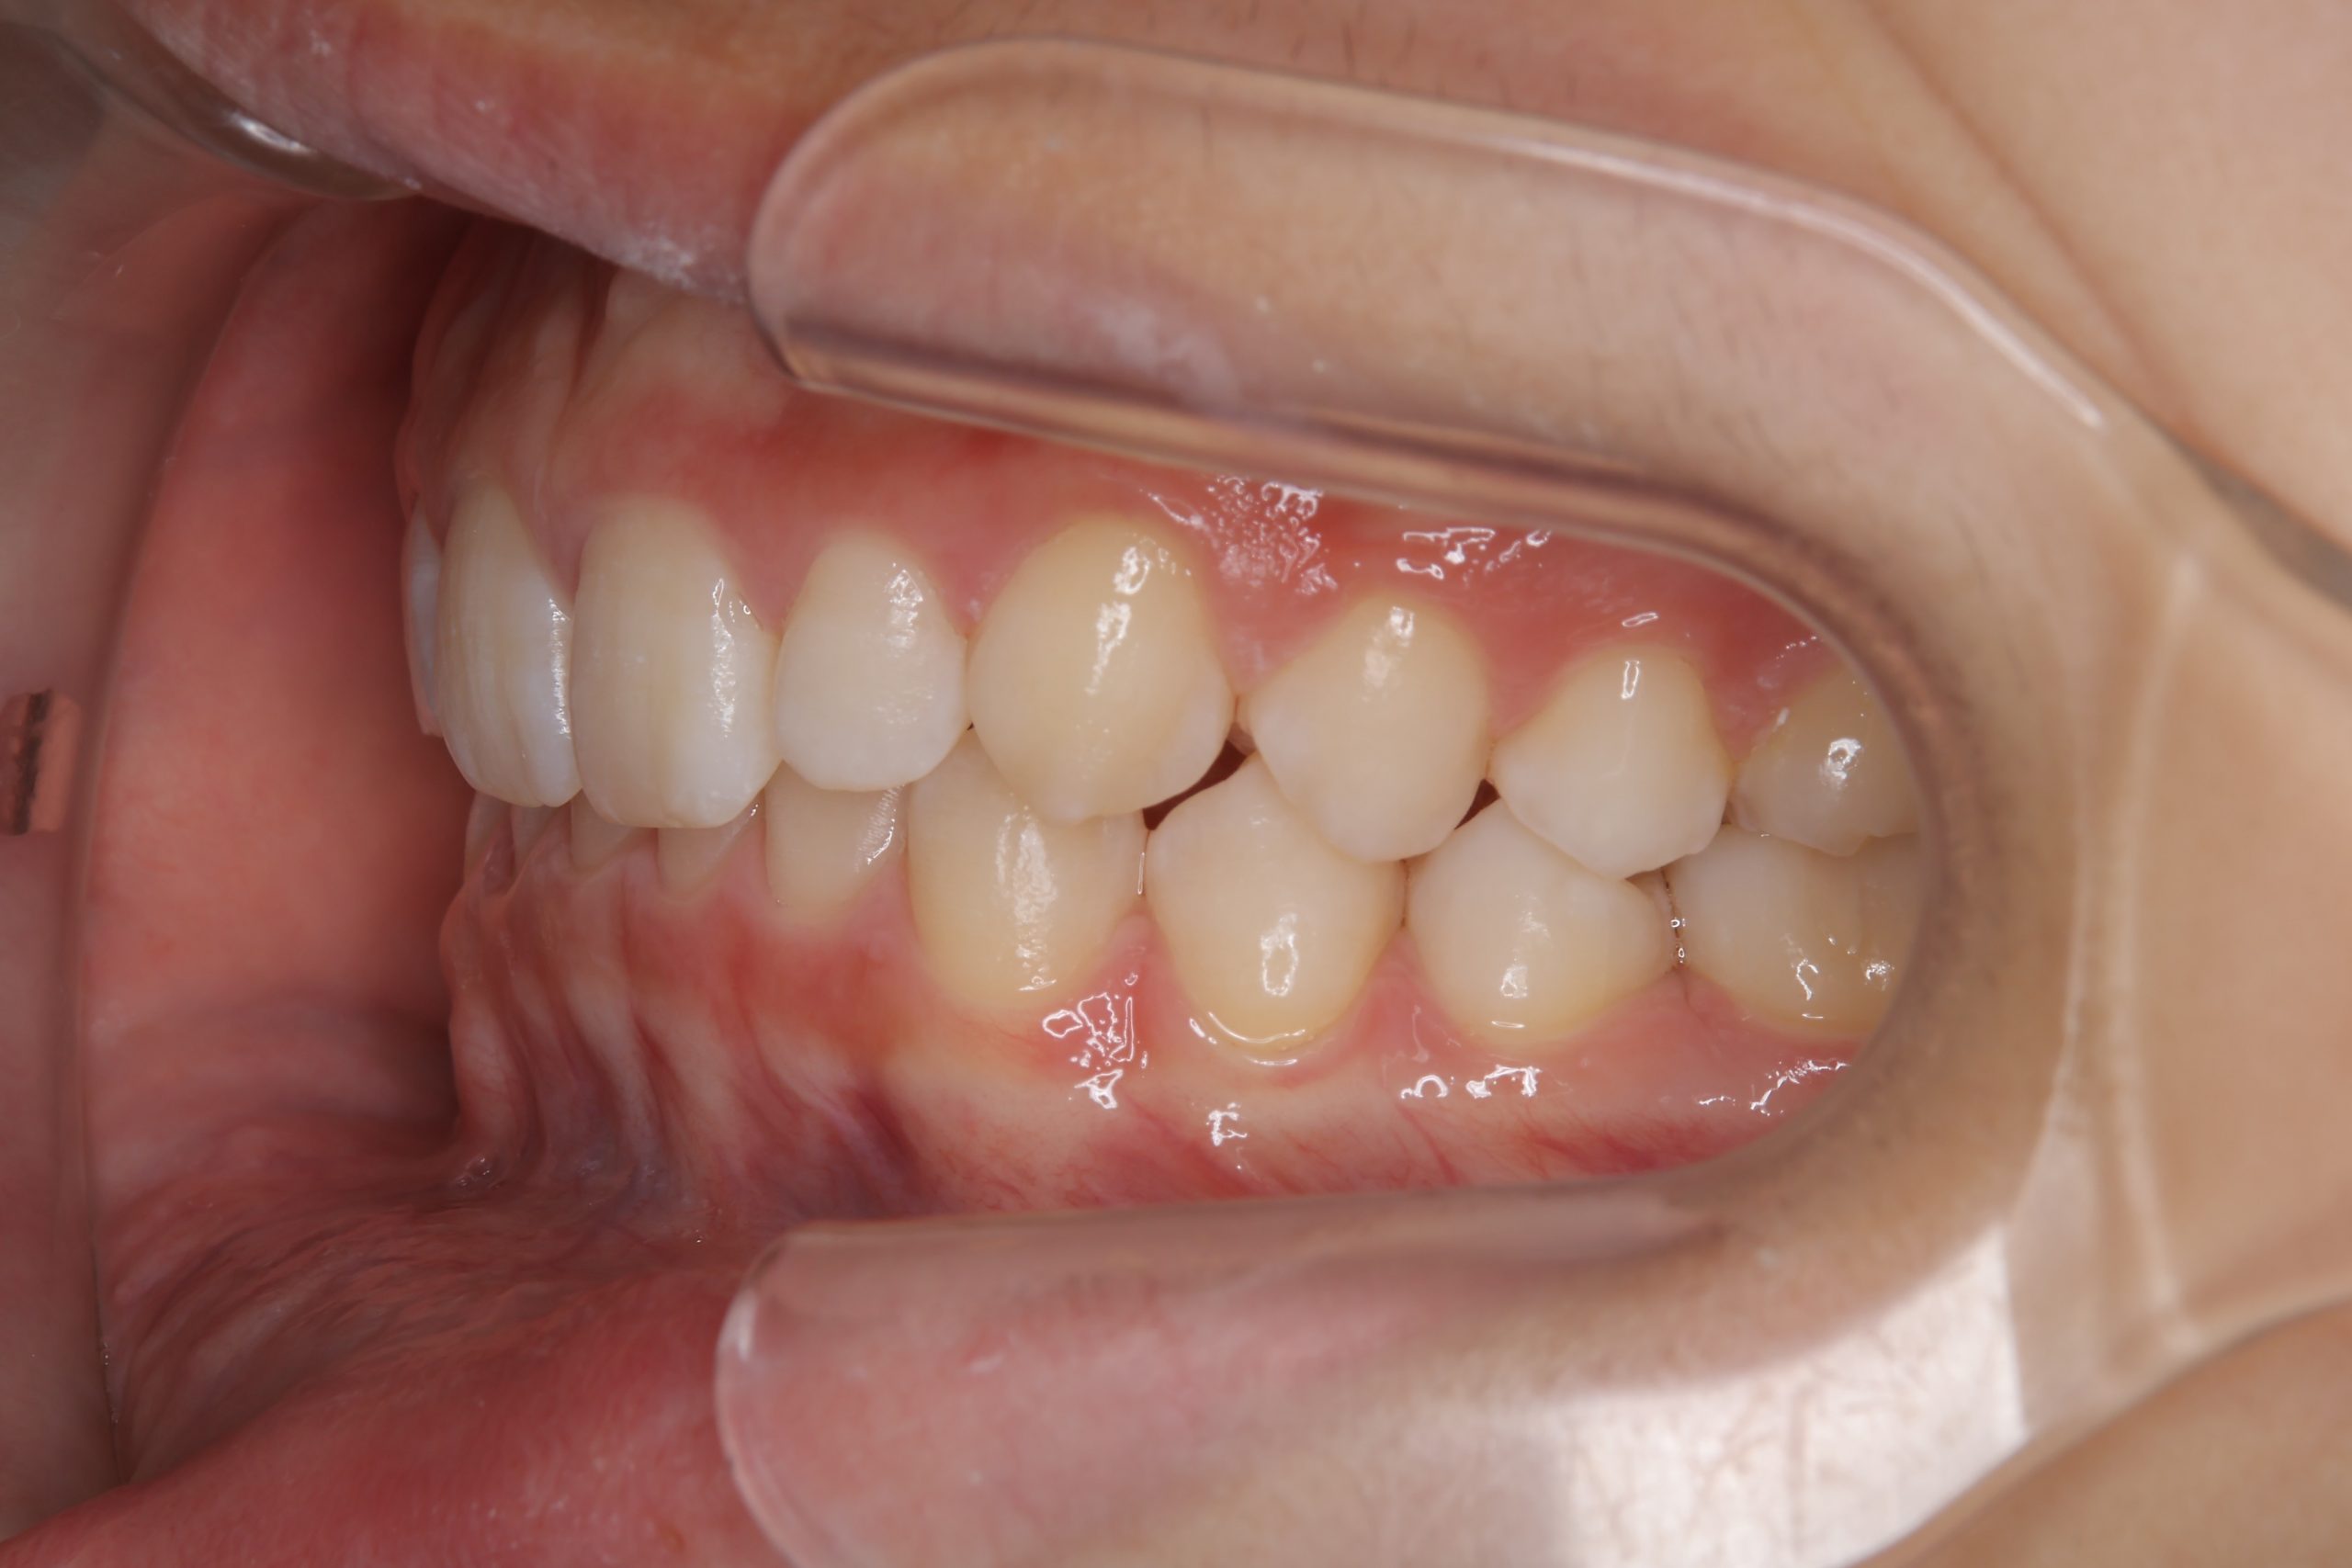

子どもの矯正治療|症例_121 Case

ビフォー

アフター

主訴 歯並び

施術内容 上顎急速拡大装置と下顎リンガルアーチを用いて上下顎骨を拡大した。

その後マウスピース型矯正装置で歯牙を配列し良好な咬合を獲得した。

治癒期間 3年11ヶ月間